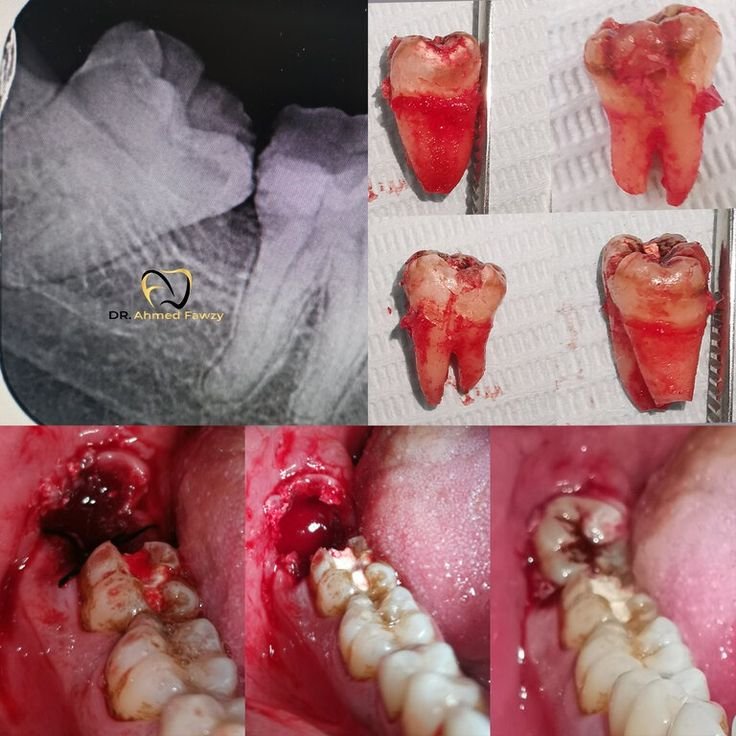

The total bill hinges on how hard the job is. A basic extraction uses simple tools and local numbing. No big cuts or deep digs. But impacted cases call for surgery. Dentists cut the gum and bone to free the tooth. They may stitch the site after. Advanced imaging helps here. X-rays or CT scans show the tooth's position and roots. This avoids damage to nerves or nearby teeth. Anesthesia adds to the price, too. Local shots numb the area. Sedation or general anesthesia eases fear for tough cases.